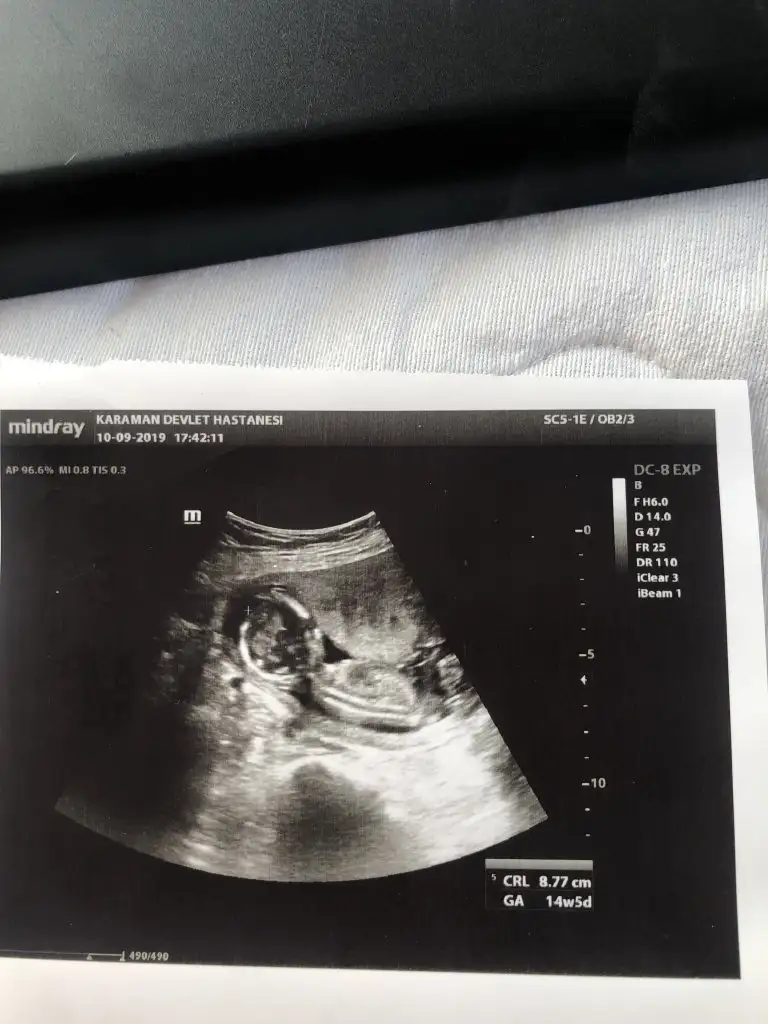

10 haftalık usg nub iki tarafa benzer şimdilik kız gibi ama degişebilir 11 yada 12 hafta usg olmalı nub içinMerhaba hanimlar,bizde 10. Haftanin içindeyiz karindan usg yorumlayabilir misiniz acaba?

Kaç haftalık tam net degil başka varsa tahmin ederimMerhaba benim için de cinsiyet tahmini yapabilir misiniz?